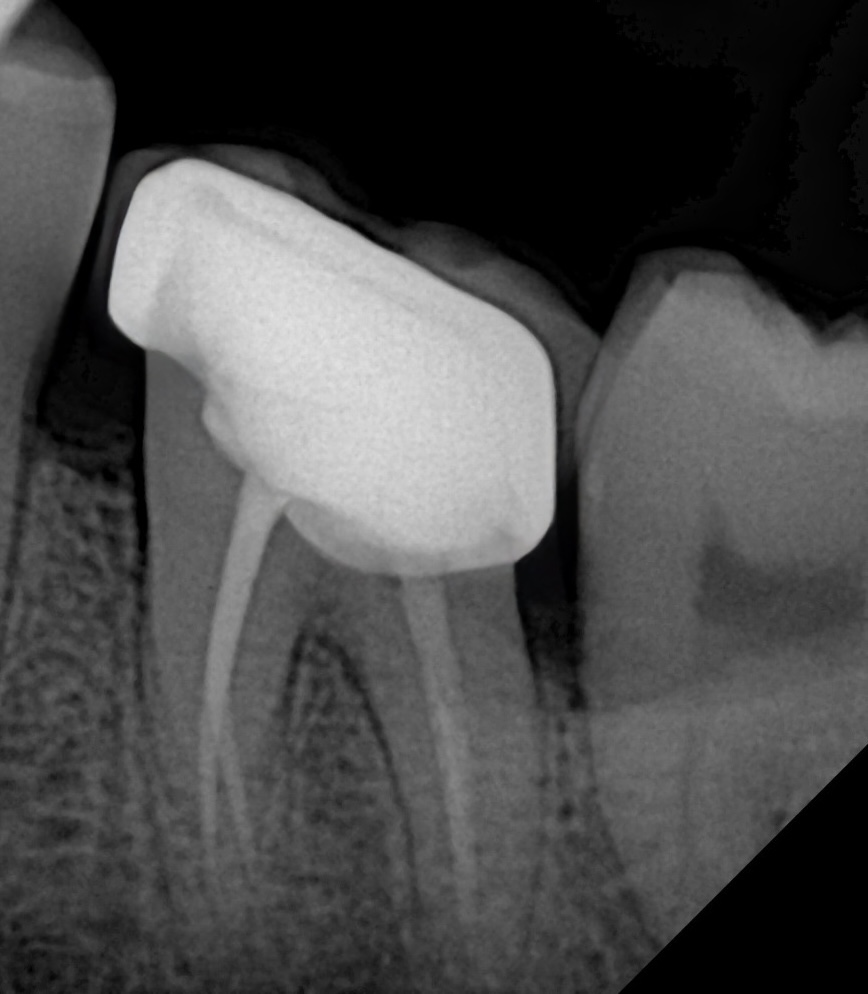

8. Final Outcome

The restored molar now exhibits:

- Stable occlusion

- Strong cuspal protection

- A perfectly sealed adhesive interface

- Natural morphology

- Reinforced internal structure

A tooth that once appeared hopeless is now functional, esthetic, and biomechanically stable.

This is the power of protocol-driven, microscope-enhanced biomimetic dentistry.